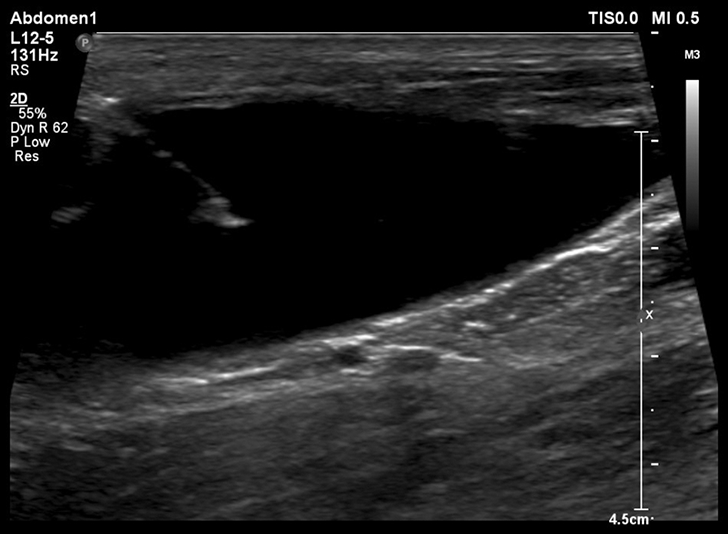

From ultrasoundstore.com

Vet Cystocentesis using ultrasound guidance Veterinary Cystocentesis Definition The needle is passed through the abdominal wall into a full bladder and urine is withdrawn directly. A sterile needle and syringe are used to collect urine from the bladder. Cystocentesis is a surgical procedure performed by a vet to collect urine directly from the bladder of small animals. The vet inserts a sterile needle through. Cystocentesis is a veterinary. Veterinary Cystocentesis Definition.